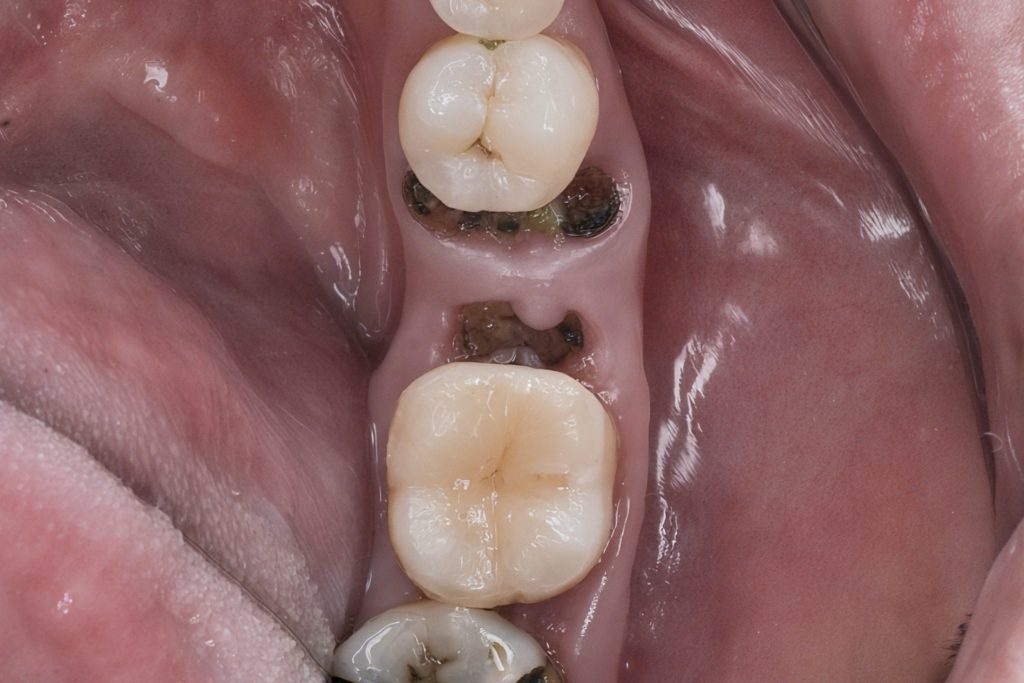

The patient presented with secondary caries beneath a failing distal composite and subgingival margin on the mandibular first molar. Adjacent premolar also exhibited proximal decay compromising contact and gingival contour (Fig 1–2). The objective was to perform a biologically respectful restoration preserving enamel and periodontal health.

Fig 1–2: Pre-operative clinical view showing extensive proximal caries and subgingival extension.